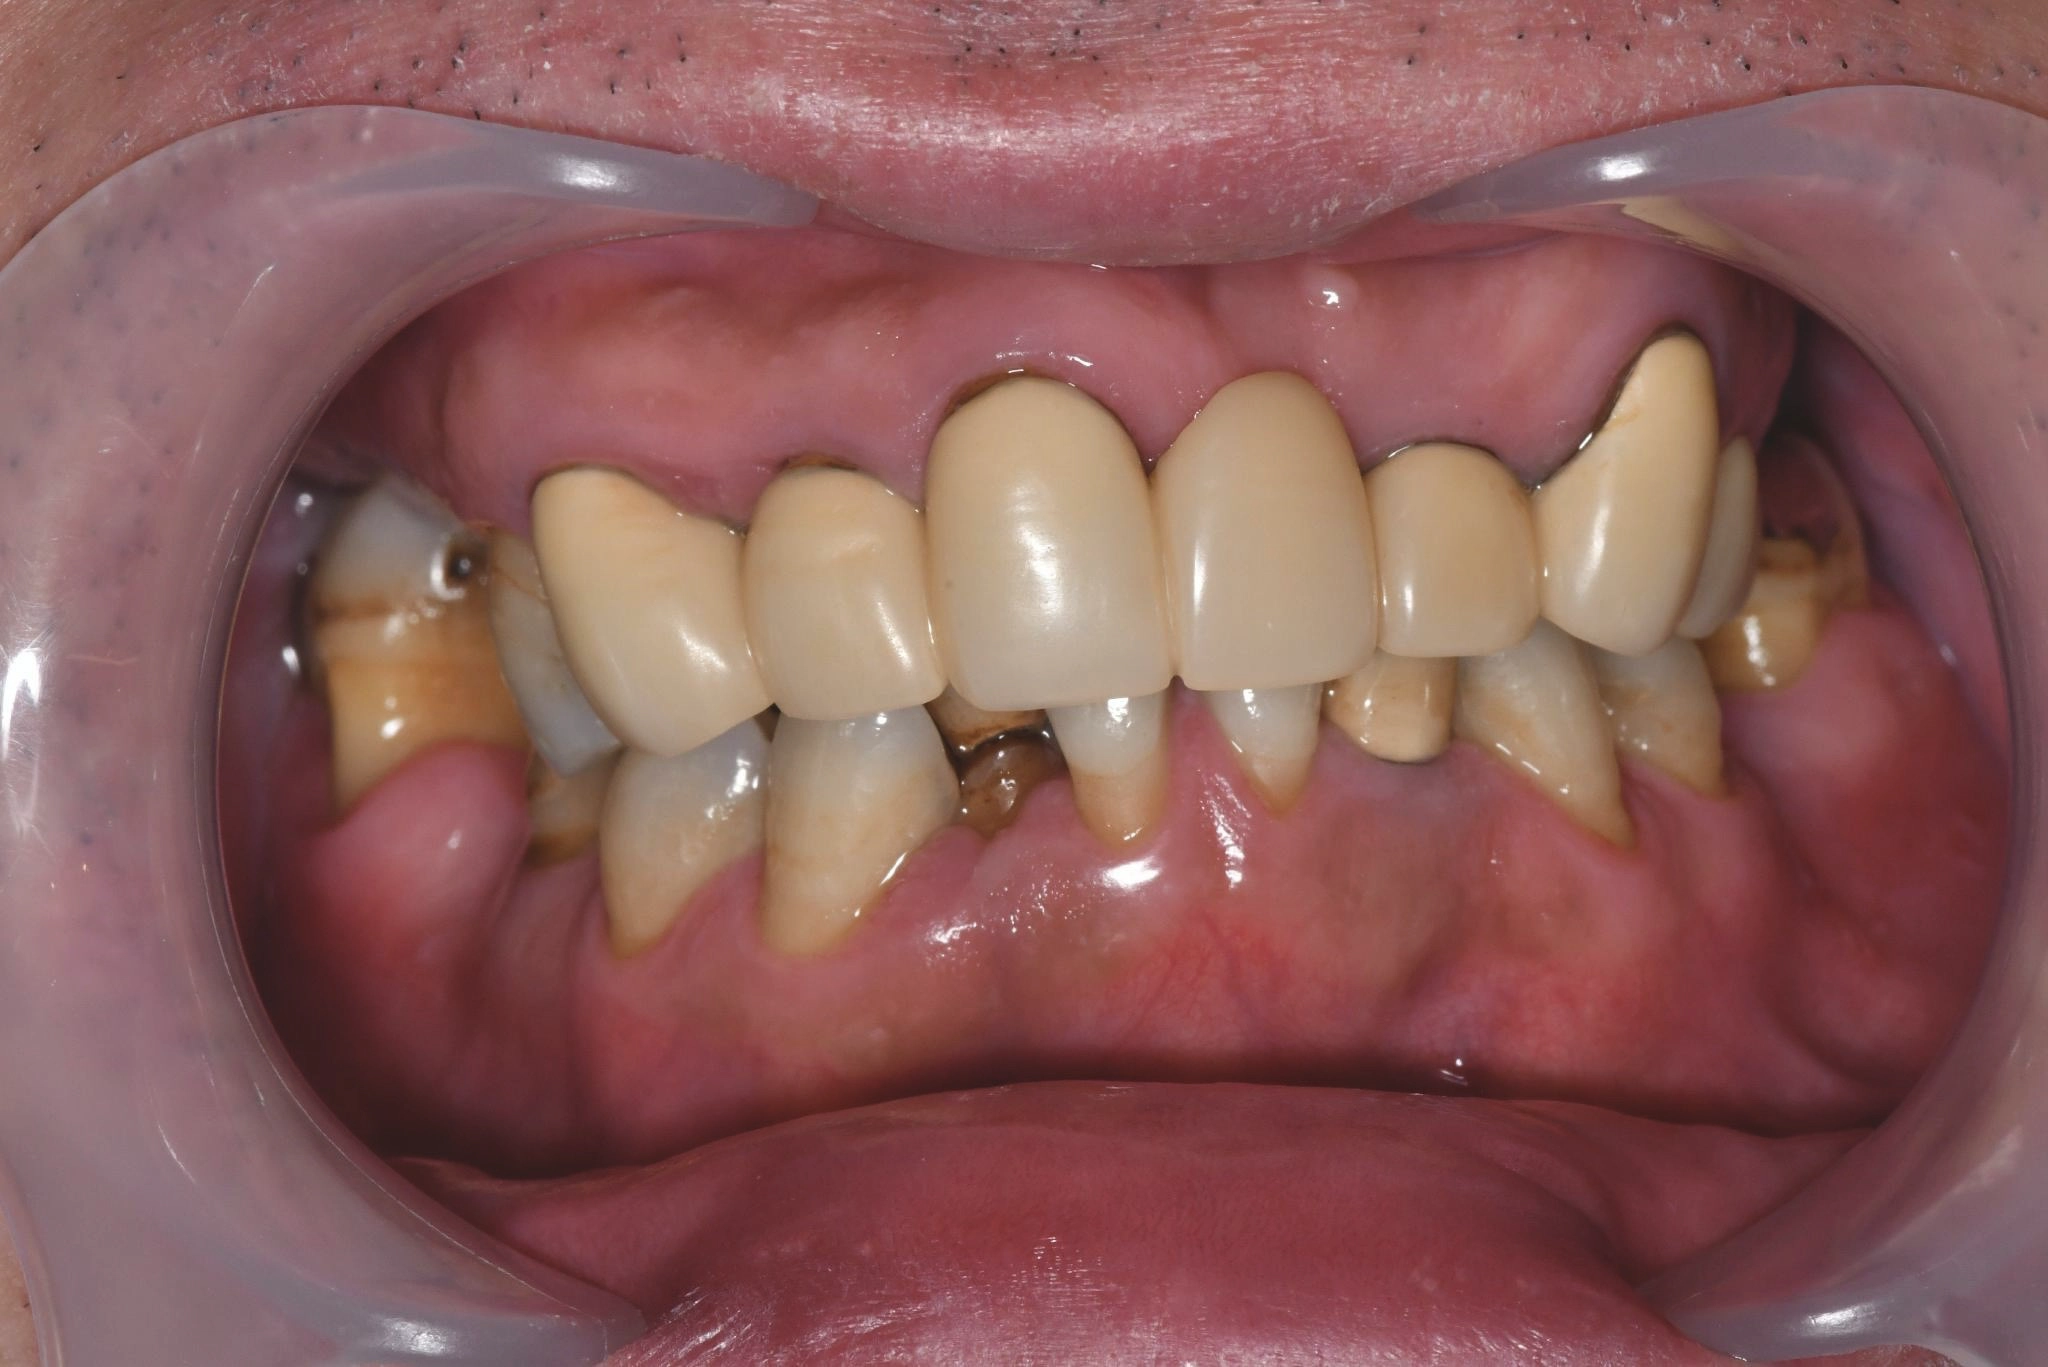

大分県 45歳(女性)

「マスクを外して人付き合いをしたい」

術前

術後

内容 :上下顎オールオン4ザイゴマ0

費用 :4,365,900円

※モニター価格

期間 :半年

リスク:出血・腫れ・痺れ・痛み

「何度も通って恥ずかしい思いを長引かせたくない」という気持ちがありましたので、治療期間が短く、たった1日で固定式の歯が入ることがとても魅力的でした。

手術に対しては強い恐怖心を持っていましたが、実際には術中の記憶はほとんどなく、痛みを感じることもなく無事に終えることができました。

これまでは口元を気にして人との接触を避けていましたが、「笑顔で話したい」という明るい気持ちになれました。